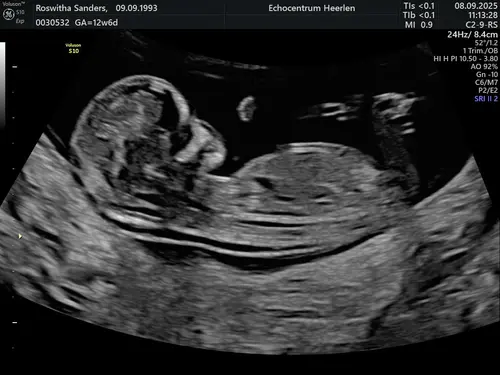

Wat denken jullie meisje of jongen?

We zullen het pas zeker weten bij de geboorte, maar mijn schoonzusje hield zich bezig met de theorieën en nu ben ik wel benieuwd wat anderen denken

Ik weet niet goed of de nub hier te zien is…

Ik zelf zie hem ook niet echt maar ook te weinig verstand van ik zal nog eens een andere erbij zetten van dezelfde echo

Oeh lastig, ik zie wel een nub maar vind het lastig om te zien of deze nu meer in een driehoek staat tov de ruggengraat of dat het recht door loopt 😅. Misschien zijn er kenners die het zien?